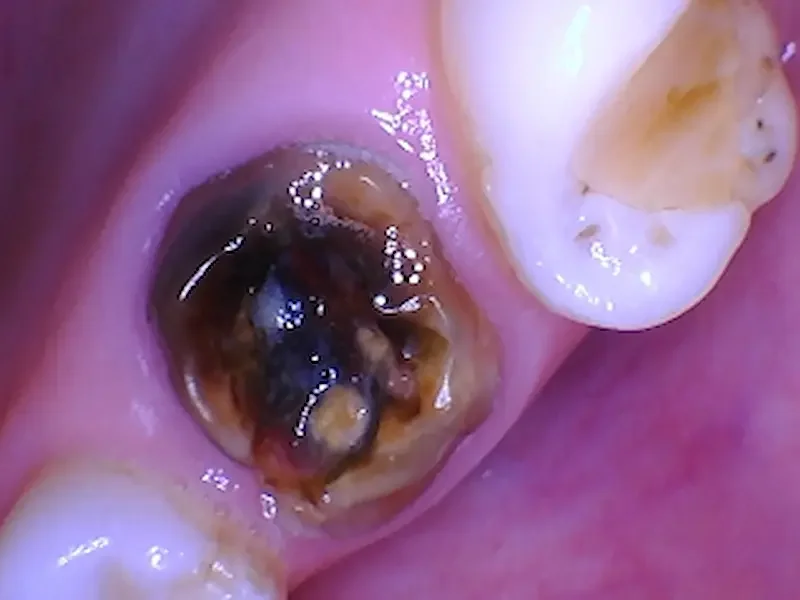

Before Procedure: Abscessed Root Canal Tooth

This case involved tooth #3, an upper molar that had an abscess caused by a large cavity. The tooth was broken at the gumline. The tooth had an old root canal as well.

Before the tooth was removed, there was an abscess visible in the X Ray. This tooth was broken at the gumline for some time, but not bothering the patient (it was not causing pain, and she could chew comfortably with her remaining teeth). But she was aware of the risks with an abscess like this, and wanted to get it taken care of.

Picture of the tooth. Notice the darkness (decay) in the center of the tooth. This is the infection’s source. There is not enough tooth left to predictably save with a crown.